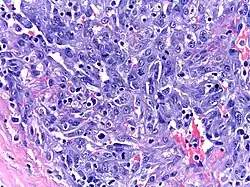

| Micrograph of HHV8-associated Castleman's Disease showing LANA-1 positive lymphoblasts in a regressed germinal center and mantle zone. LANA-1 stain. | |

Unlike the other subtypes of Castleman disease, UCD and iMCD, which can present with a spectrum of features on microscopic analysis (histology) of tissue biopsied from an enlarged lymph node, only a plasmablastic pattern of histologic features has been described in HHV-8-associated MCD. Plasmablastic features are similar to the plasmacytic features seen in iMCD and UCD, with both demonstrating increased plasma cells in interfollicular spaces. Plasmablastic features are differentiated from plasmacytic features by increased numbers of plasmablasts in follicular mantle zones.[10]

Staining with latency-associated nuclear antigen (LANA-1), a marker for HHV-8 infection, is typically positive.[11]